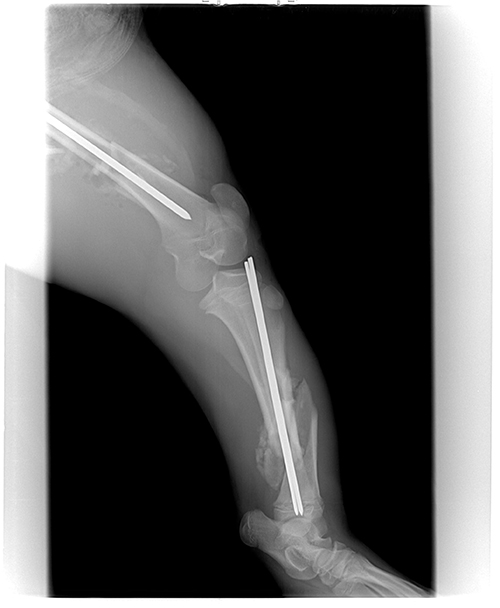

By day 14 our veterinarian felt he was strong enough to set his leg. Both large bones in his left hind leg were badly broken (see pictures above). The operation took almost five hours. She put rods through the center of the bones. It was a very big job, but everything went well.